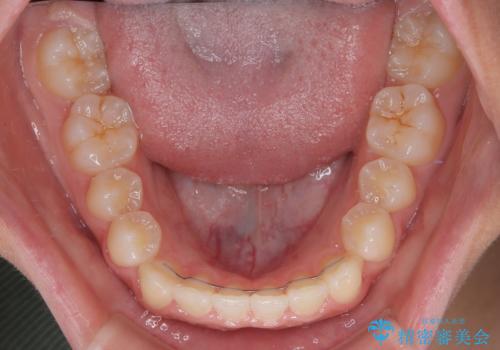

- 前歯の隙間を気にして来院された患者様です。

口元の突出感があり、小臼歯4本を抜歯して口元を引っ込める矯正治療も提案しましたが、本人は口元の突出感は気になっていないとのことで、インビザラインにて隙間やデコボコを改善することとしました。

軽度の歯列不正であったため、廉価版のインビザライン・モデレートパッケージにて治療を終えることができました。